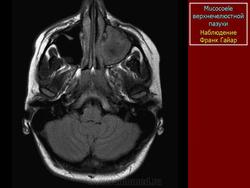

Мукоцеле

1.mu_.slayd364.jpg2.mu_.slayd365.jpg3.mu_.slayd366.jpg

3.c.slayd27.jpg4.c.slayd28.jpg